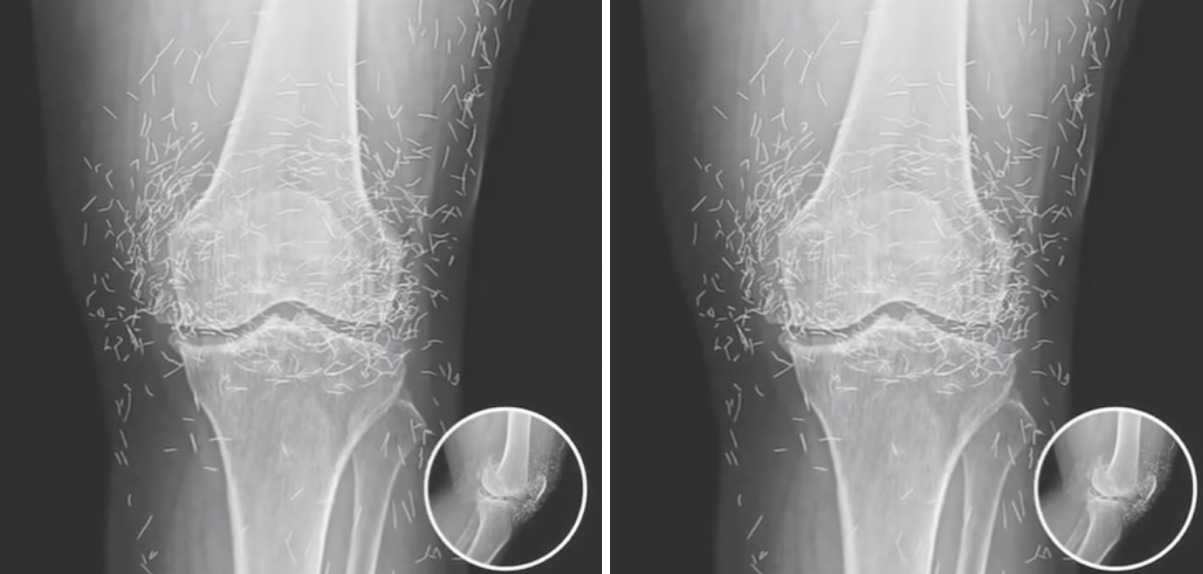

Toen de röntgenfoto op het scherm verscheen, hield het team even de adem in. In plaats van een standaard beeld van versleten gewrichten, zagen de artsen tientallen dunne gouden draadjes die zich in haar knie hadden genesteld. Wat op het eerste gezicht leek op een technisch artefact, bleek al snel een bijzonder echt beeld te zijn.

De röntgenbeelden werden opnieuw gecontroleerd door verschillende specialisten. Alle bevestigden hetzelfde: de knie van Marianne zat vol fijne gouden naaldjes. De ontdekking was zeldzaam en trok meteen de aandacht binnen het medisch centrum.

De technicus die de scan had uitgevoerd, controleerde de apparatuur en het bestand nogmaals. Alles bleek correct. De gouden deeltjes waren geen reflectie of fout, maar fysieke objecten. Ze lagen keurig verspreid rond het gewricht, alsof ze met precisie waren geplaatst.

Toen de röntgenbeelden werden geanalyseerd, werd duidelijk dat de draadjes netjes verspreid zaten in het zachte weefsel van het gewricht. De specialisten waren verbaasd, maar ook gefascineerd door de precisie waarmee dit ooit was uitgevoerd.